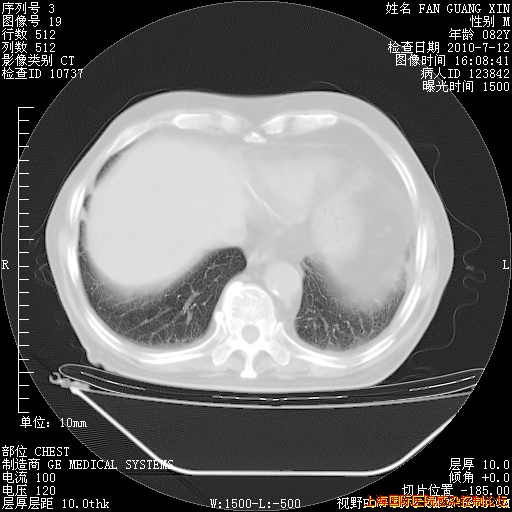

今天复查CT

今天CT

整整相隔30天的肺部CT好像有所好转啊。甲强龙减量第3天,需要观察体温。

海管,自昨日你和我通完话后,不知您岳父消化道症状有无缓解?体温怎样?阅读7.12日胸部ct,个人认为目前激素治疗是有效的,甲强龙减量是适宜的。因在抗痨治疗,需密切观察肝功、肾功能和血常规。不过,老年、长期住院和大量使用激素,很担心菌群失调发生